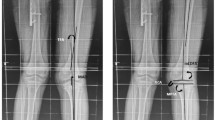

(1)

Mechanical tibiofemoral angle (mTFA) or hip-knee-ankle angle represents the angle between the mechanical axis of the femur and the mechanical axis of the tibia in the frontal plane of the knee (varus position negative, valgus positive) (Fig. 1a); this value is automatically calculated by the EOS 3D software.

Fig. 1 Mechanical tibiofemoral angle: a Represented in 3D EOS reconstructions of pathological lower limbs from our database. FMA femoral mechanical axis, mTFA mechanical tibiofemoral angle, LBA load-bearing axis, TMA tibial mechanical axis. b Mean values ±2 standard deviations (SD) of the mTFA. c Scatterplot and linear regression of mTFA with age. Dashed lines represent the 95 % confidence interval (CI) upper/lower limits of the linear regression coefficient

In boys, the mTFA increased from 5.5° to 8.0° between the ages of 2 and 3, decreased to -0.9° by the age of 8 years, fluctuated at ∼0.3° and finally decreased to −1.8° at the age of 15–16 years. In girls, it increased from 2.5° to 4.9° between the ages of two and three, decreased to 0.9° then showed a slight increase until finally fluctuating at ∼0.5° (Table 3, Fig. 1).